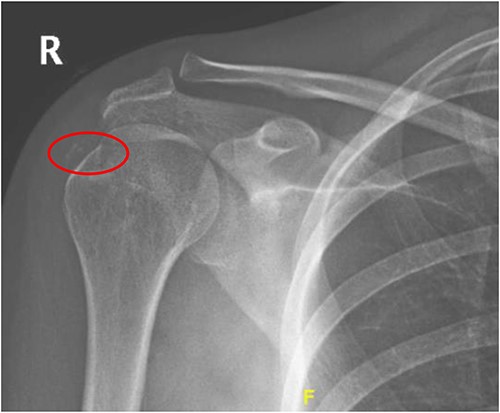

Radiographs showed calcification around the region of insertion of the supraspinatus tendon on the humeral head. No fracture lines or surrounding soft tissue swelling were noted. Radiographs of the right shoulder are shown in Fig. 1.

Radiograph of right shoulder showing calcification around the insertion of supraspinatus tendon.